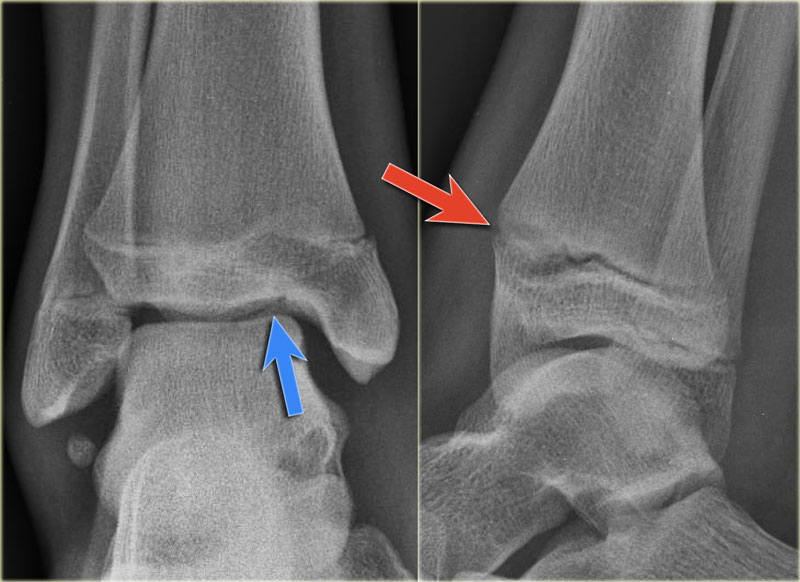

Growth Plate Fractures Explained with XRay Examples YouTube Growth Plate Fracture Cast But because they are still growing, a child's bones are. It might take longer if they had a more severe type of. What is a growth plate fracture? some growth plate fractures are treated with a cast or splint, but if the fracture is more severe, the broken pieces of bone are put. a growth plate fracture happens. Growth Plate Fracture Cast.

The Radiology Assistant Ankle Special fracture cases Growth Plate Fracture Cast It might take longer if they had a more severe type of. a growth plate fracture happens when an accident or overuse causes a break in the growth plate tissue. most kids need to wear a cast for around a month after a growth plate fracture (usually four to six weeks). the bones of children and adults. Growth Plate Fracture Cast.